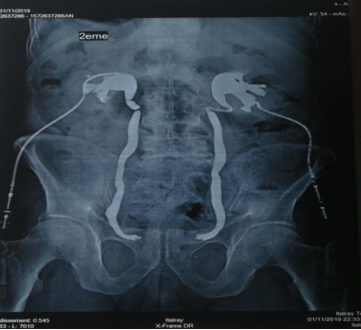

To prevent patient from going into metabolic disorders, hemodialysis was performed in 27 patients (67.5%). Internal diversion of urine by mounting a JJ catheter was initially attempted in 40% of the cases. In case of attempt failure, or in case of locally advanced pelvic tumors, percutaneous nephrostomy was performed with a success rate of 100%.